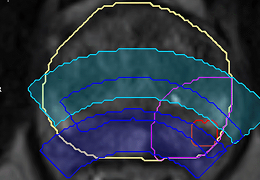

Before the procedure: Identify challenges and choose the optimal treatment modality using MR, PSMA PET Imaging, and 3D ablation energy

models.

In the operating room: Focus on executing the pre-plan.